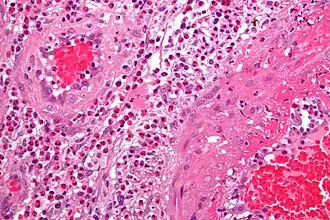

La vasculitis engloba todos aquellos síndromes y enfermedades que cursan con inflamación de los vasos sanguíneos (vénulas, capilares y arteriolas de mediano y gran calibre) tanto de órganos específicos como generalizadas.[1][2]

Patogenia

Los dos mecanismos más conocidos por los que se produce una vasculitis son:

- Inflamación de origen inmunitario

- Mediadas por el sistema del complemento

- Mediadas por anticuerpos (síndrome de Goodpasture)

- Mediadas por inmunidad celular

- Invasión directa de las paredes vasculares por agentes patógenos